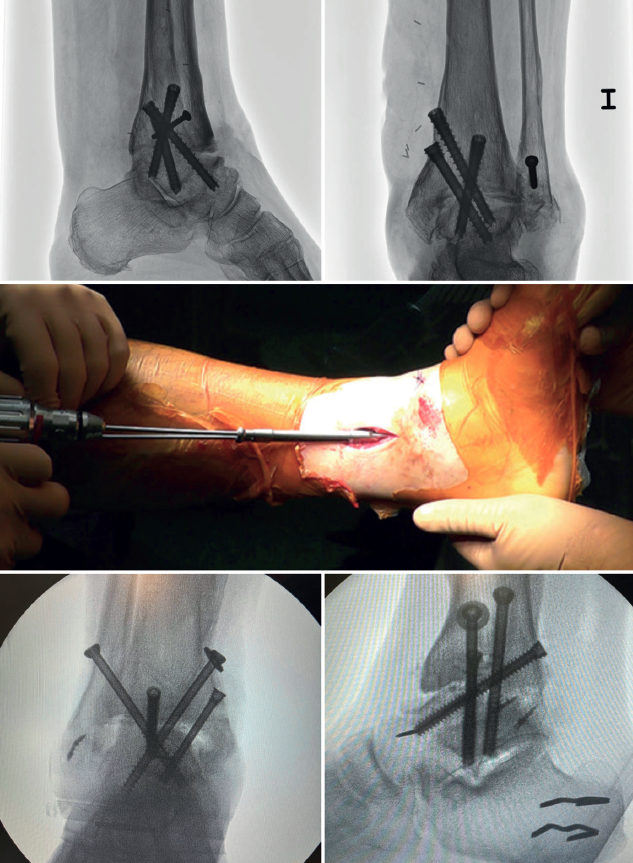

En las artrodesis de tobillo por vía artroscópica, el uso de tornillos a compresión colocados de forma percutánea es la técnica de elección (Figura 5).

La mayoría de los autores consideran el uso de tornillos canulados (de 3 a 4) como el método idóneo de fijación. Los diámetros de los tornillos escogidos oscilarán entre los 6 y los 7 mm. Con esta técnica se consigue del 85 al 100% de fusión y entre el 84 y el 95% de satisfacción del paciente(19).

Van Dijk, Kerkhoffs et al.(20) reportan excelentes resultados con el uso de 3 tornillos como método estandarizado para las artrodesis de tobillo.

Configuración y colocación de los tornillos

Dependiendo de la deformidad y en función de la planificación preoperatoria, se realiza la colocación de los tornillos, comenzando con el tornillo de compresión que contrarresta la deformidad.

Es decir, en las artropatías con componente de varo empezaríamos por un tornillo lateral, mientras que en las desalineaciones en valgo la recomendación es colocar el primer tornillo desde medial. El segundo tornillo debería ser del lado opuesto al primero. Ambos deben realizar la compresión adecuada entre superficies articulares(17).

En general, se utilizan un mínimo de 3 tornillos. El tercer tornillo es el denominado home run, cuya importancia destacan en su trabajo Holt et al.(21). Se dirige cruzando el tobillo desde la parte posterior de la tibia hasta el cuello del astrágalo. Puede utilizarse un cuarto tornillo a modo de aumentación del primero, del que contrarresta la deformidad principal.

Goetzmann et al.(22), en su serie de revisión de 111 casos, respaldan el uso de al menos 3 tornillos para la fijación de la artrodesis tibioastragalina artroscópica. Añadir un tercer tornillo parece asociarse con un menor riesgo de pseudoartrosis y un menor tiempo de consolidación. Estos efectos pueden atribuirse a una mayor estabilidad del constructo.

Glick, Myerson(23) et al. publicaron que la configuración que conferiría mayor rigidez a la osteosíntesis es con 2 tornillos desde medial y 1 desde lateral.

Se toman radiografías definitivas anteroposterior, de mortaja, lateral del tobillo, dorsoplantar y oblicua del pie para confirmar la correcta reducción, la posición y la longitud de los tornillos, en especial del tornillo home run (Tabla 3).